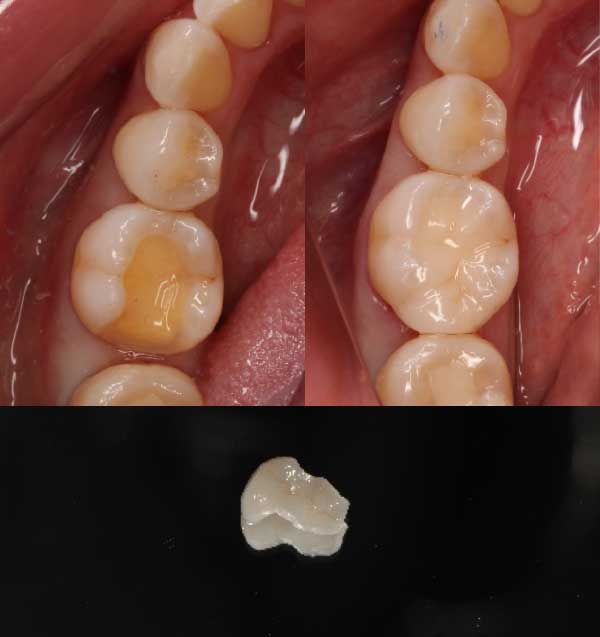

さらに歯の内部に虫歯が侵入し、黒い虫歯の範囲が広がっています。虫歯により健康な歯の残量が少なくなり、歯の修復範囲も大きくなります。

・インレー修復

こちらは保険治療で銀歯が入っています。

虫歯を取り、歯を削ったところに、元の歯の形に合わせたインレーを製作し、歯に装着して治療が終わります。

こちらは自費治療でセラミックの白い歯が入っています。

銀歯の時と同じように、歯の形に合わせて製作したセラミックインレーを歯に装着して治療が終わります。